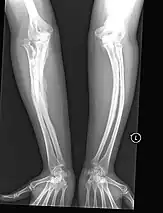

- Type V – Having the same clinical features as type IV, it can be clinically distinguished by observing a "mesh-like" appearance to a bone biopsy under a microscope. Type V can be further distinguished from other types of OI by the "V triad": an opaque band (visible on X-ray) adjacent to the growth plates; hypertrophic calluses (abnormally large masses of bony repair tissue) which form at fracture sites during the healing process; and calcification of the interosseous membrane of the forearm,[50] which may make it difficult to turn the wrist.[1]: 429 Other features of this condition may include pulled elbow, and, as in other types of OI, long bone bowing and hearing loss.[64] Cases of this type are caused by mutations in the IFITM5 gene on chromosome 11p15.5.[64][49] The separation of type V from type IV OI, its clinical type, was initially suggested even before its genetic cause was known, by Glorieux et al. in 2000.[50][65] Type V is relatively common compared to other genetically defined types of OI—4% of OI patients at the genetics department of the Brazilian Hospital de Clínicas de Porto Alegre were found to have it.[66]

Diagnosis is typically based on medical imaging, including plain X-rays, and symptoms. In severe OI, signs on medical imaging include abnormalities in all extremities and in the spine.[97] As X-rays are often insensitive to the comparatively smaller bone density loss associated with type I OI, DEXA scans may be needed.[5]: 1514